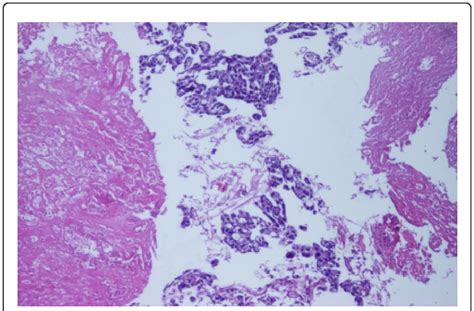

Alright, let’s talk about the diagnosis of an infiltrative Wachstum tumor. Diagnosing these tumors involves a few different steps, and the goal is to figure out exactly what’s going on and how far the tumor has spread. The first step usually involves a physical exam and a review of your medical history. Your doctor will ask about your symptoms, any risk factors you have, and your family history of cancer. Next, your doctor may order imaging tests, such as X-rays, CT scans, MRI scans, or PET scans. These tests provide detailed images of the inside of your body and can help identify any tumors and assess their size and location. A biopsy is often necessary to confirm the diagnosis. During a biopsy, a small sample of tissue is removed from the tumor and examined under a microscope by a pathologist. This helps determine the type of cancer cells present and whether they are infiltrative. Depending on the type of tumor and its location, other tests may be necessary. These tests could include blood tests to check for tumor markers, which are substances produced by cancer cells, or endoscopic procedures to visualize and sample tissues from inside the body. Staging is a crucial part of the diagnostic process. Staging helps determine the extent of the cancer’s spread and helps guide treatment decisions. The staging process typically involves a combination of physical exams, imaging tests, and biopsy results. The stage of the cancer is often described using the TNM system. In this system, “T” refers to the size and extent of the primary tumor, “N” refers to whether the cancer has spread to nearby lymph nodes, and “M” refers to whether the cancer has spread to distant sites in the body. The results of all these tests will be analyzed by a team of healthcare professionals, including oncologists, radiologists, and pathologists. They’ll work together to determine the diagnosis, stage the cancer, and develop a treatment plan. Diagnosing an infiltrative Wachstum tumor can be a complex process, but it’s essential for providing the right treatment and improving outcomes. Trust your medical team and don’t hesitate to ask questions if anything is unclear. They’re there to guide you through every step of the process.